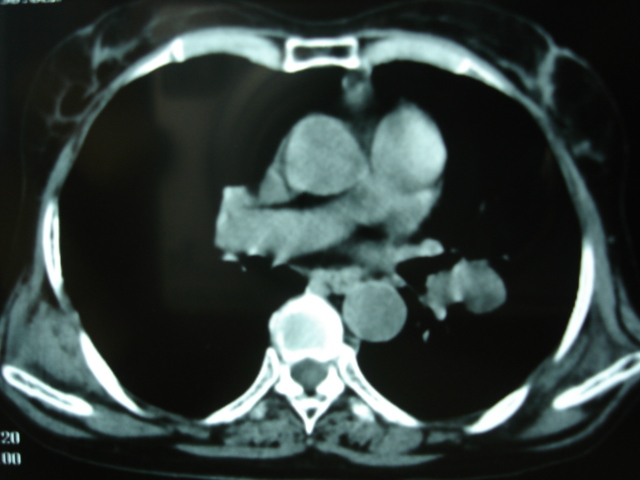

以下是引用卜一在2009-9-7 19:51:00的发言:[br][br] 1 左侧胸内甲状腺占位-多考虑甲状腺腺瘤! 2、左肺门占位-建议增强扫描以便明确性质。 3 慢支并感染! [br]

以下是引用shibing在2009-9-7 20:40:00的发言:[br]左侧胸内甲状腺占位-多考虑甲状腺腺瘤! 2、左肺门占位-建议增强扫描以便明确性质。 3 慢支并感染! [br]